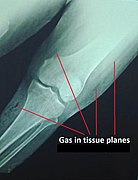

• Magnetic resonance imaging to visualize necrotized subcutaneous tissues

• X-rays for air pockets in affected tissues